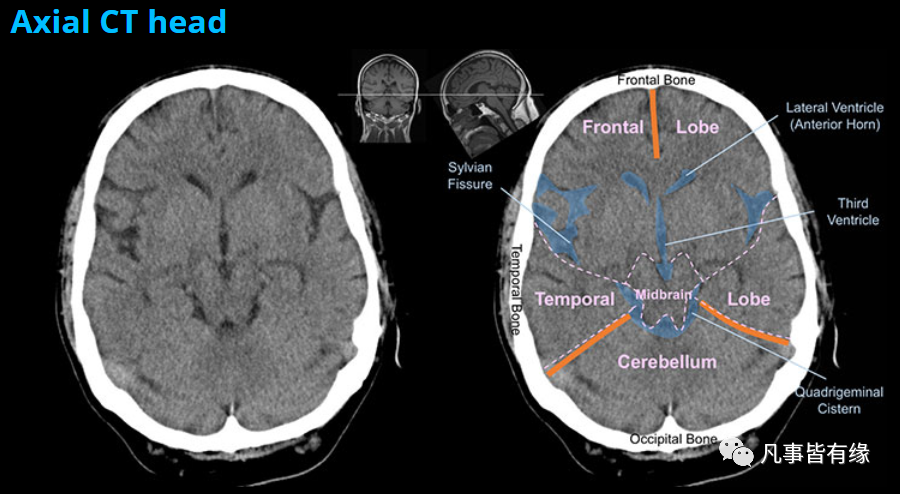

颅脑CT每天都在看,每天都在学习和辨认着这些既熟悉又陌生的神经结构,每每看到好的标注图,都觉得欣喜。

来源:凡事皆有缘(吴晓安)